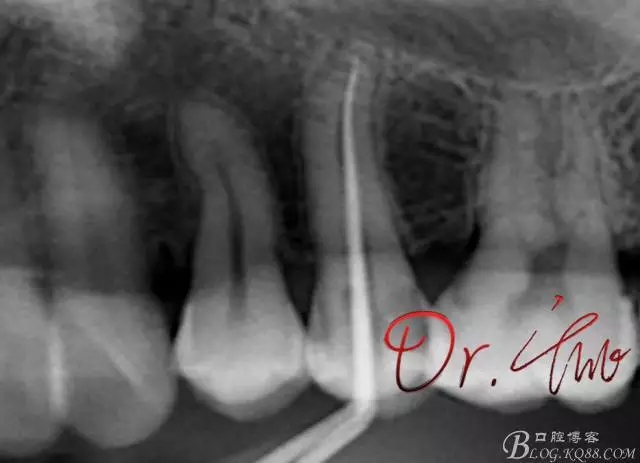

初診照

640.webp.jpg

拍片確定長(zhǎng)度

640.webp (1).jpg